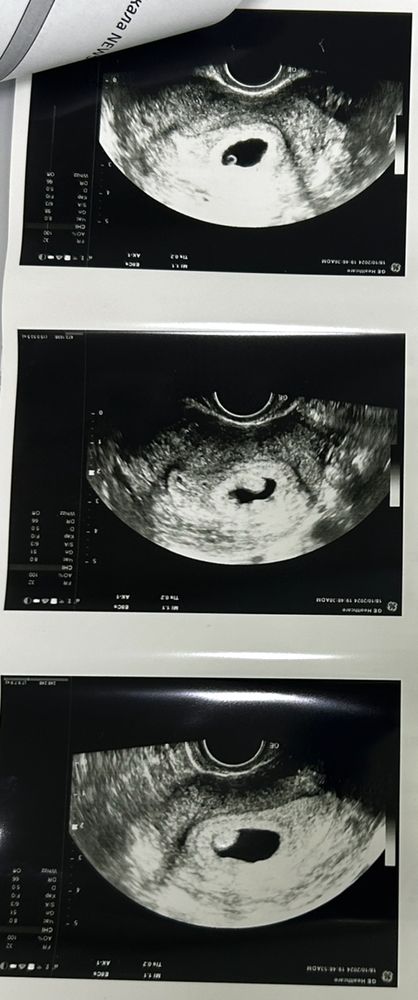

При анэмбрионии хгч растет как при нормальной беременности??

Нет эмбриона, при плодном яйце 23-24мм, и желтечного мешечка тоже нет, 35дпп.

Сегодня сдала хгч, высокое 86238 на 35дпп, и было на 19дпп-6803, на 13дпп-889.

Значит хгч растет при анэмбрионии так же как и при нормальной беременности?

Узи в двух местах сказали то же самое(((